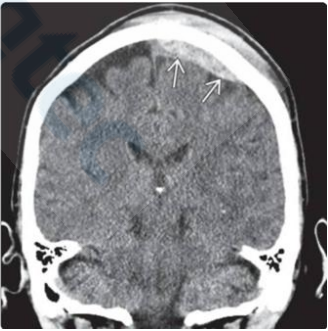

No traumatismo cranioencefálico, a correta identificação das lesões estruturais é de suma importância para determinar o tratamento a ser empregado. Considerando esse fator, analise a Figura 2 abaixo:

Figura 2

Considerando um desvio da linha média de 6 mm e sem lesões >25 mL, assinale a alternativa correta sobre a classificação de Marshall apresentada no exame e sua definição.